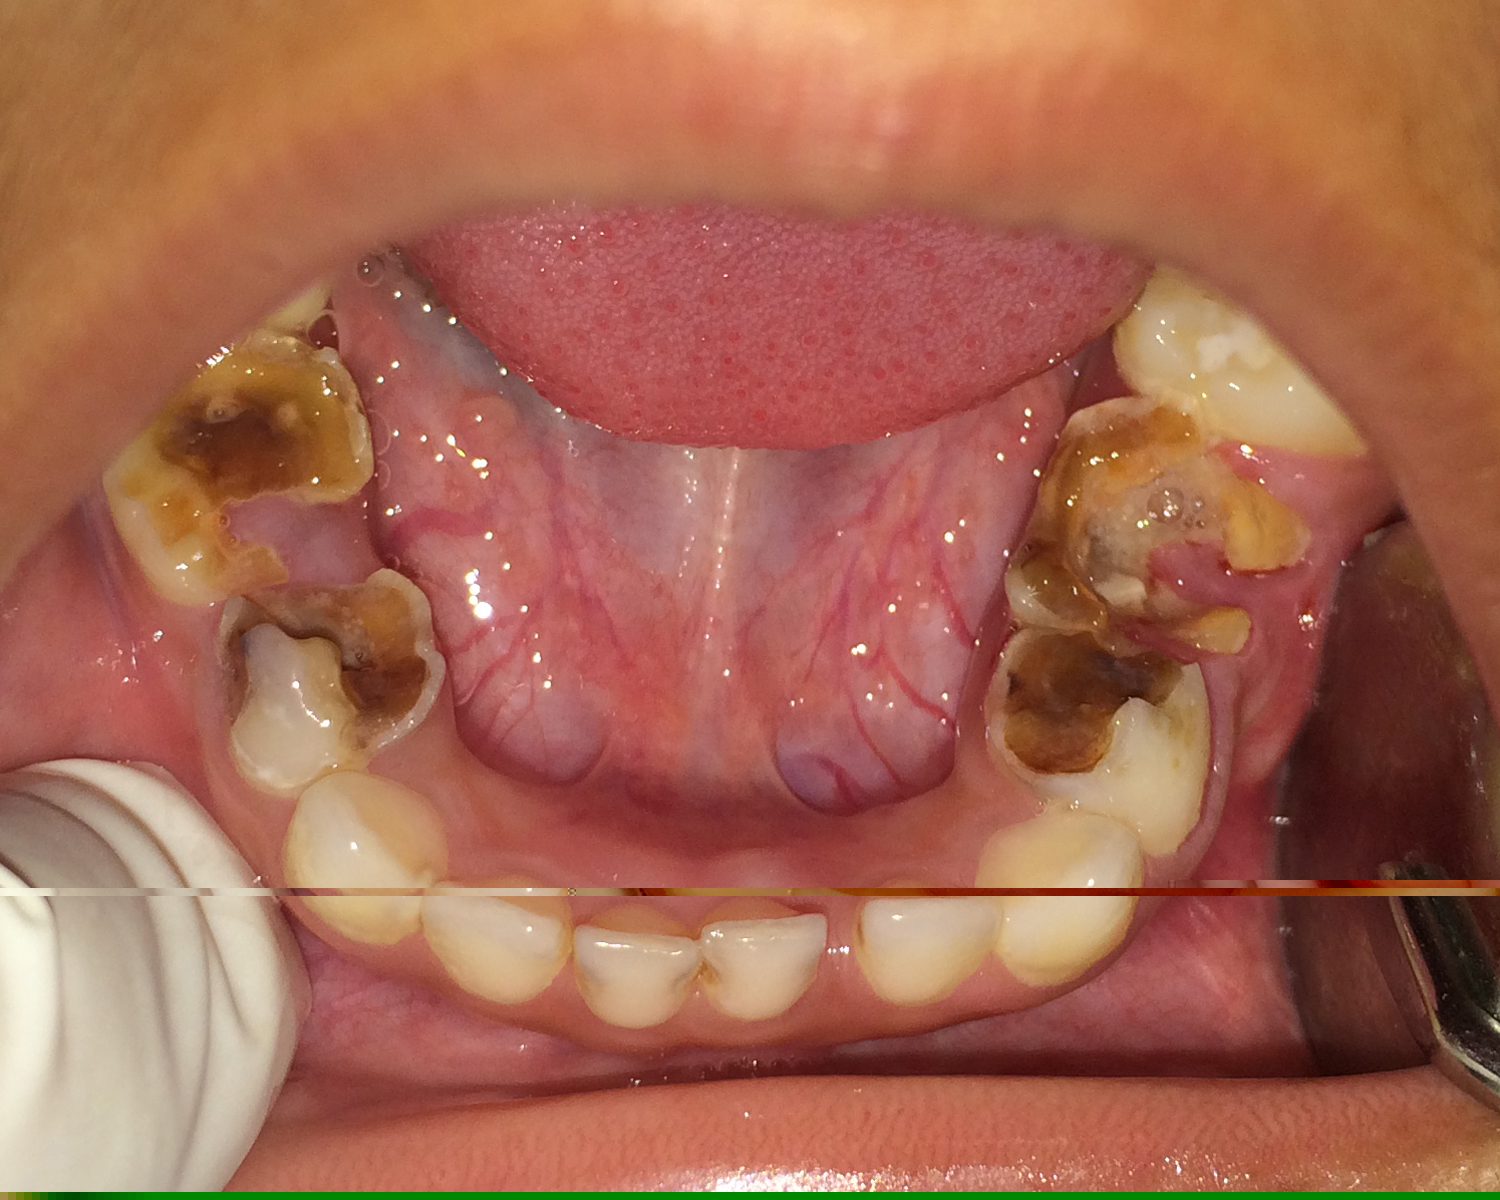

Perforasi iatrogenik merupakan salah satu resiko yang sering terjadi dalam perawatan endodontik yang disebabkan oleh kesalahan operator. Perforasi dapat terjadi pada apeks, lateral atau korona. Perawatan untuk perforasi dapat dilakukan dengan bedah atau non bedah. Prognosis dari perforasi endodonti dipengaruhi oleh beberapa faktor antara lain adalah waktu terjadinya perforasi, lokasi perforasi dan besarnya perforasi. Tujuan laporan kasus ini untuk melaporkan perawatan perforasi korona pada pulpektomi gigi decidui. Kasus seorang anak laki-laki usia 6 tahun datang bersama ibunya dengan keluhan gigi bawah belakang kanan sering sakit tiba-tiba sejak tiga bulan yang lalu. Diagnosis pada gigi molar pertama kanan rahang bawah adalah karies profunda kelas I dengan pulpitis irreversible. Perawatan yang dilakukan adalah pulpektomi. Dalam proses perawatan terjadi perforasi korona di mesial yang disebabkan oleh trauma bur preparasi saat dilakukan pembukaan atap pulpa. Perawatan pulpektomi tetap dilanjutkan dengan menutup daerah perforasi dengan zinc phosphat cement dan diakhiri dengan tumpatan tetap stainless steel crown (SSC). Kesimpulan dari laporan kasus ini yaitu perawatan perforasi korona dengan non bedah pada pulpektomi gigi decidui mempunyai prognosis yang baik. Perawatan dilakukan dengan bahan tumpatan yang memiliki ketahanan terhadap saliva dan tidak mengiritasi pulpa ataupun gingiva.